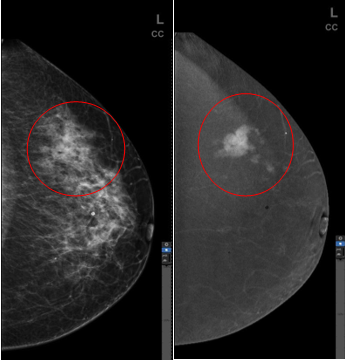

乳腺高清对比增强技术(CESM HD)检查时,患者在乳腺摄影前经静脉注射碘剂,在同一位置,不同的能量下(低能和高能)进行图像采集、减影、融合与重建。生成有效消除背景及腺体组织,仅保留碘剂代谢异常的乳腺病变影像。该技术结合了数字化乳腺摄影与对比剂使用的优点来检测乳腺病变,可实现对实质肿块以及微钙化的显示。临床实践证明CESM不但可显著提高乳腺X线摄影的敏感性,特异性,降低召回率及活检穿刺率,而且敏感性和MRI(核磁共振)一致,利用这项全球独有领先技术,增加了医生在乳腺疾病尤其是乳腺癌筛查及诊断信心,可以更好地为病人服务。

病例一

(左图)传统数字乳腺X线摄影(FFDM)

(右图)乳腺高清对比增强技术(CESM HD)

左乳外象限局限致密影

病理:左乳浸润性导管癌